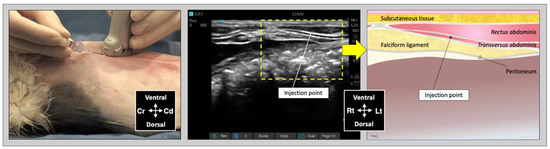

For the subcostal TAP injection, the transducer was initially positioned perpendicular to the long axis of the cat, immediately caudal to the xiphoid process, over the ventral midline. After identification of the linea alba, the transducer was slid laterally and parallel to the costal arch and oblique to the midline (Figure 3). The needle was introduced in-plane in a ventromedial-to-dorsolateral orientation and continuously visualized while advanced towards the TAP until its tip was inserted into the fascial plane between the mm. rectus abdominis and transversus abdominis. Then, an injectate volume of 0.25 mL/kg was administered by TAP-SL.

Figure 3. Ultrasound transducer position, needle puncture site, sonographic image, and schematic representation of the subcostal TAP injection in a cat cadaver; Cd, caudal; Cr, cranial, L, lateral; Lt, left; M, medial; Rt, right. Adapted from: Garbin, M.; Benito, J.; Ruel, H.L.M.; Watanabe, R.; Monteiro, B.P.; Cagnardi, P.; Steagall, P.V. Pharmacokinetics of bupivacaine following administration by an ultrasound-guided transversus abdominis plane block in cats undergoing ovariohysterectomy. Pharmaceutics 2022, 14, 1548. https://doi.org/10.3390/pharmaceutics14081548 (accessed on 1 August 2022).